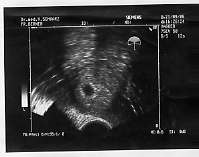

21.9.06

19.10.06

16.11.06

14.12.06

5.2.07

CTG am Geburtstag um ca. 8.00